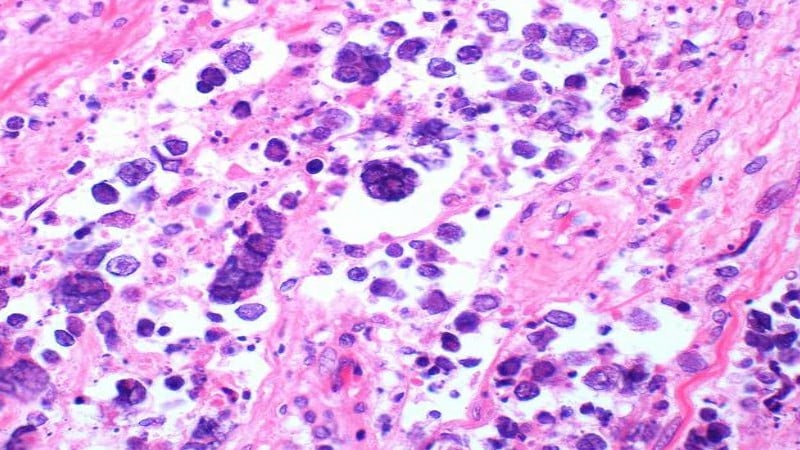

They cause little sores or blisters to appear on your anus, vulva, vagina, cervix, penis, scrotum, buttocks, inner thighs, lips, mouth, throat, and sometimes eyes. They can be sore, itchy, and oozing.